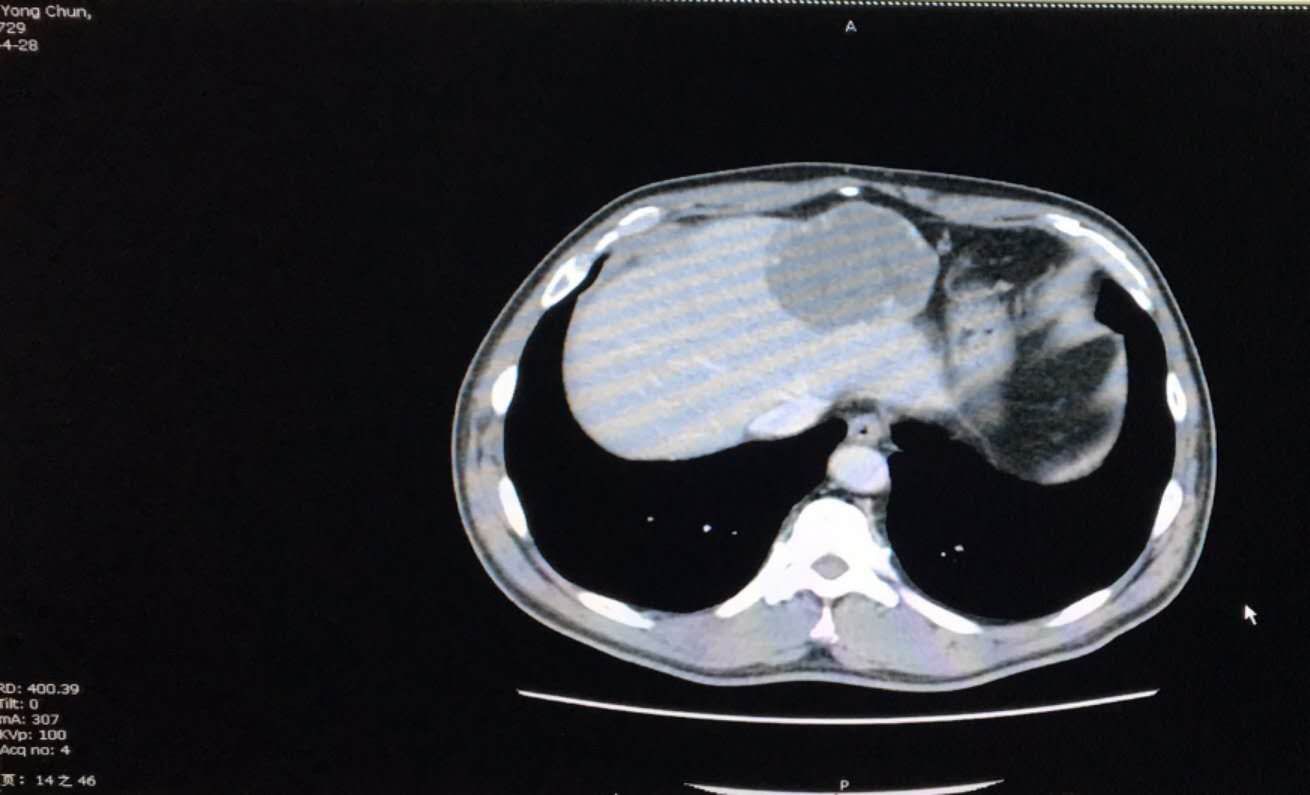

哈市62岁的李大爷体检时偶然发现患上了肝血管瘤,CT检查显示肝左外叶(II、III段)占位约10cm×8cm×6cm如芒果大小,与第一肝门等重要血管关系密切,考虑为巨大肝血管瘤。这个体内大隐患让李大爷和家人都心惊胆战。自从查出血管瘤,李大爷身心俱疲,连走路都小心翼翼,生怕肿瘤破裂。用他的话来讲,体内犹如安装了一个定时*弹炸**,害怕随时引爆。心急如焚的家人走访多家医院比较治疗方案和专家的意见,最后决定在哈尔滨市第一医院普外二科手术治疗。